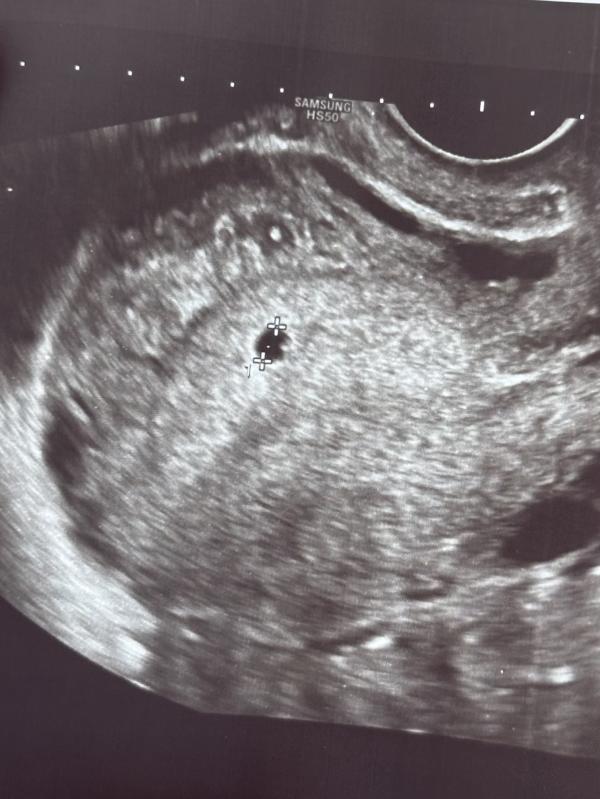

Не видно эмбриона на 5-6 неделе беременности: нормально ли это?

Ну привет, кроха❤️ срок сегодня по менструации 5 н 6 д. Плодное яйцо 3,6 мм, виднеется желточный мешочек. Эмбриончика пока не видно, ждём ещё